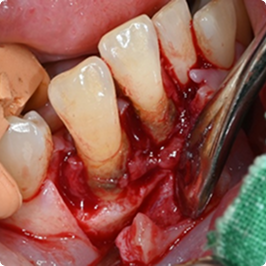

수술적 잇몸 치료 - 잇몸 수술

치아 뿌리 깊숙이 자리한 치석을 비수술적 치료만으로 제거하기 어려울 때,

잇몸을 절개해 직접 시야를 확보한 뒤, 숨어 있는 치석과 염증 조직을 깨끗이 제거하는 치료입니다.

서울하늘에치과 잇몸 살리기 치료 사례

01

오랜 잇몸병으로 발치 직전의 치아, 잇몸 재생 치료로 자연치아 유지

치료 전

치료 후

치료 내용

• 좁고 깊은 치주낭(잇몸 주머니), 염증과 치아 흔들림, 타 치과에서 발치 권유

• 치주수술 + 엠도게인 적용으로 잇몸과 잇몸뼈 재생 유도

• 치료 후 치주낭 깊이 감소, 잇몸 회복 및 흔들림 안정